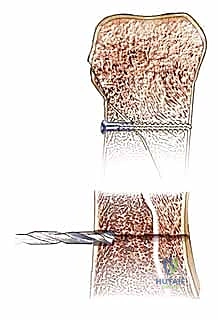

3. التثبيت داخل النقي (Intramedullary Fixation):

تُستخدم هذه التقنية الحديثة لبعض الكسور العرضية في السلاميات، حيث يتم إدخال سلك أو مسمار دقيق داخل التجويف العظمي (النقي). توفر هذه الطريقة ثباتاً جيداً دون التأثير على الأنسجة الرخوة المحيطة بالعظم.